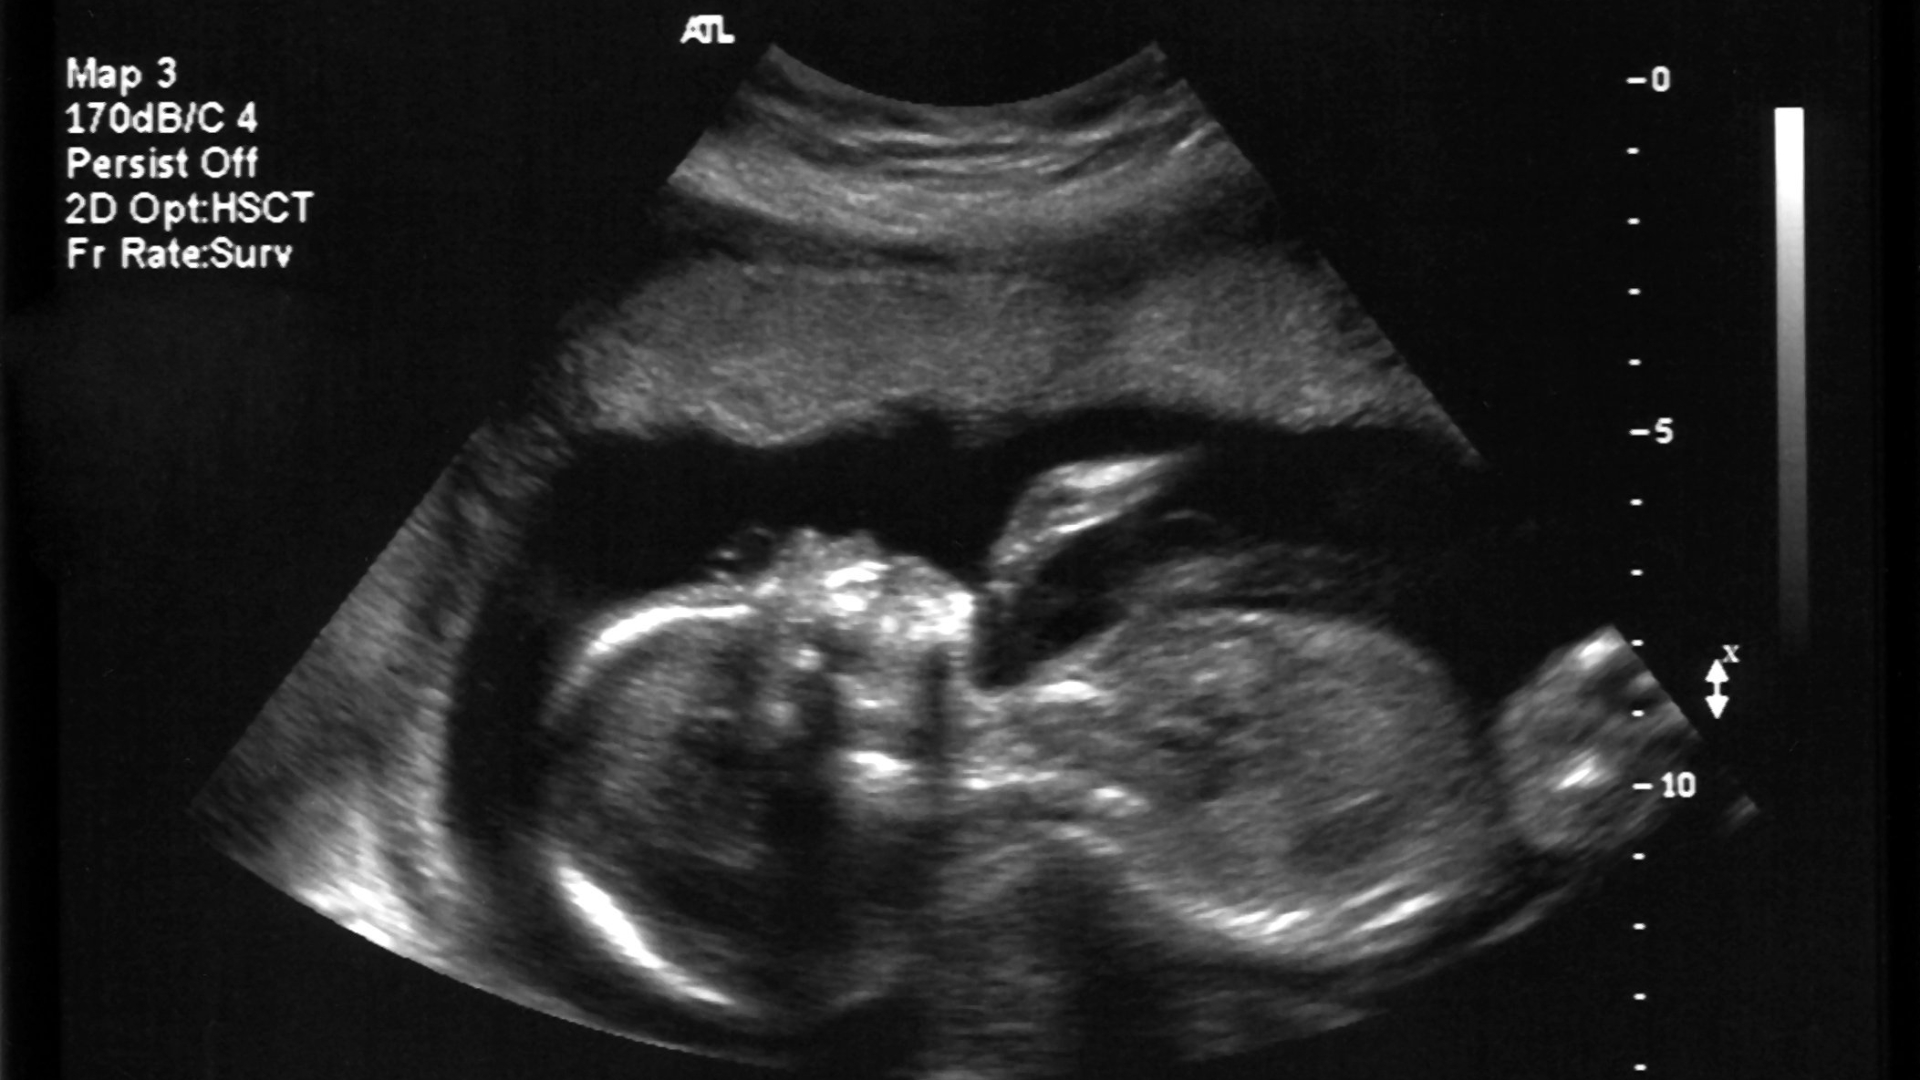

Để xác định chắc chắn, mẹ nên đến cơ sở y tế thực hiện xét nghiệm dịch âm đạo. Các phương pháp như test Nitrazine, test Ferning (quan sát hình dạng tinh thể muối dưới kính hiển vi) hoặc siêu âm đo lượng ối sẽ giúp phân biệt chính xác tình trạng này.

Khám thai định kỳ: Kiểm tra cổ tử cung, siêu âm đánh giá nước ối và phát hiện sớm các dấu hiệu bất thường.